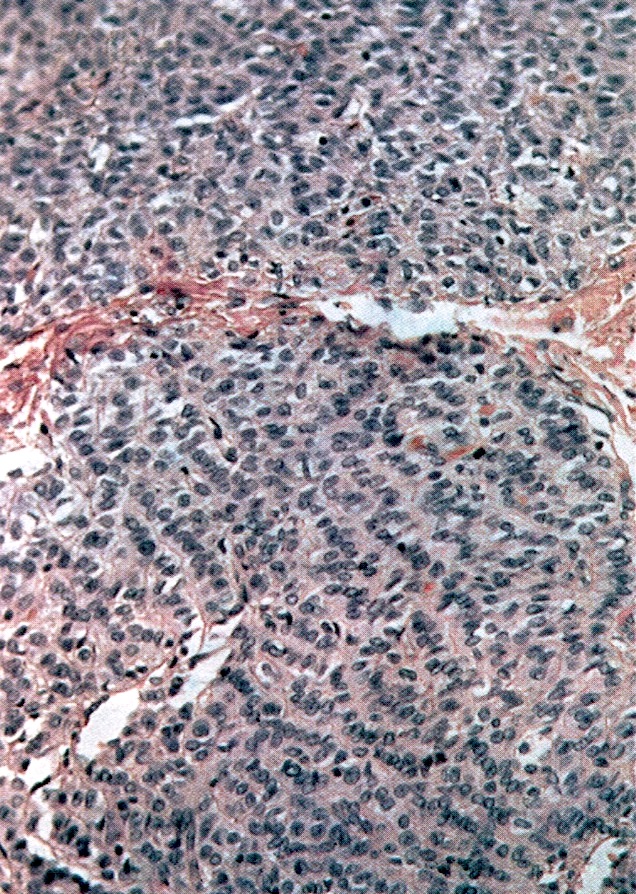

- Small, bland, cuboidal to polygonal cells with scant cytoplasm and pale, uniform angulated and usually grooved nuclei (coffee bean)

- Various patterns, including diffuse (the most common), trabecular and corded, insular, microfollicular (resembling Call-Exner bodies of the Graafian follicles: small follicle-like structures filled with eosinophilic material) and macrofollicular (the least common)

- Luteinized adult type (such as during pregnancy): rare (1%) if extensive (> 50%), plump cells with moderate to abundant eosinophilic cytoplasm, conspicuous nucleoli, no nuclear grooves, myxoid or edematous stroma; may resemble steroid cell tumor

- Mitotic activity is usually not brisk (< 3/10 high power fields)

- Rarely (2%) show focal or multifocal areas of atypical cells with enlarged hyperchromatic bizarre, some multinucleated, suggestive of degenerative change and not associated with adverse outcome (Int J Gynecol Pathol 1983;1:325)

Microscopic (histologic) images

Contributed by Shabnam Zarei, M.D. and Sharon Bihlmeyer, M.D.

AFIP images